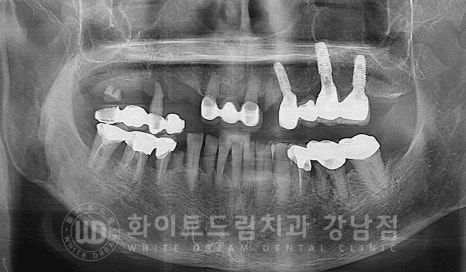

환자분의 초진 x-ray 사진입니다.

타 치과에서 치료를 받으신 20번대 임플란트가 확인되고

그 외 자연치아들은 심하게 흔들리며 치주 질환으로 출혈과 고름이 동반되고 있는 상태였습니다.

특히 10번대 브릿지의 상태가

구강 검진 시 기구로 살짝 건드리니 브릿지가 빠져버릴 정도로

상태가 정말 좋지 못했답니다.

브릿지 지대치 하나는 부러진 상태이고, 남은 지대치가 겨우 버티고 있는 상태였는데

검진시 기구로 살짝 건드리니 지대치가 자연 발거되버렸답니다.